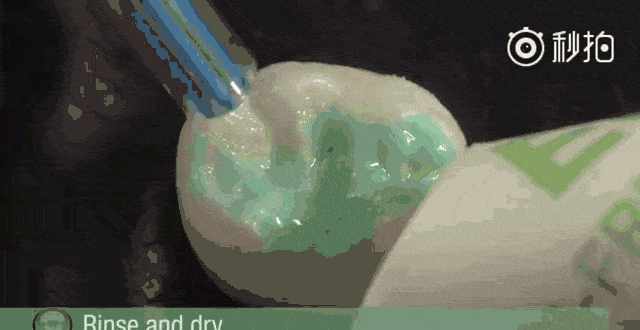

4.窝沟封闭怎么做?

很多家长会担心孩子不配合进行窝沟封闭,但是,做窝沟封闭是没有疼痛感觉的,只要给予引导,孩子大多都能接受。

家长还可以提前在家让孩子认识窝沟封闭的过程,其实就是“给牙齿穿上一件新衣服”这么简单。

1.清洁牙面

2.把牙面冲洗干净,干燥牙面

3.涂液体材料让牙齿表面变粗糙

4.再次冲洗干净,干燥牙面

5.涂窝沟封闭剂

6.用特殊光照,使窝沟封闭剂变硬